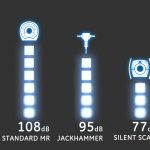

İlk olarak GE Explorer cihazı hastaların çekim sırasındaki rahatlıklarını yukarı taşımış bulunmaktadır. Daha hızlı çekimler, daha az ses ve daha rahat yatış pozisyonları sayesinde hastaların rahat bir ortamda bulunmaları sağlanmaktadır.

Signa Explorer SilentScan Teknolojisi